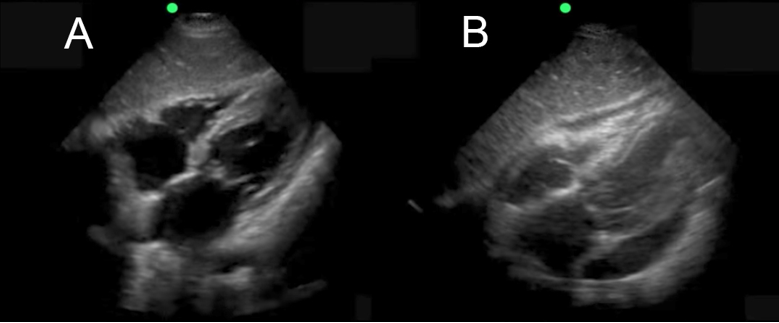

eFAST Subxiphoid View Fluid Image

A. Normal

B. Abnormal Fluid Collection